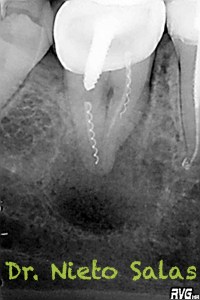

Nos remiten a la clínica a una paciente con un tratamiento previo de endodóncia realizado ya hace unos 5 años y que presenta una agudización del proceso. Se trata de un fracaso endodoncico por una falta de sellado tanto coronal como apical, en el que en el espacio intra-conductos nos encontramos dos léntulos, y en el acceso a los mismos un perno prefabricado.

Los puntos fuertes serán la retirado del perno y de los léntulos, a priori, no muy complicado, pero todo puede cambiar dentro de los conductos. Nuestro objetivo en la primera sesión será llegar a determinar la longitud de trabajo de los diferentes conductos, conformarlos y colocar nuestro Hidróxido de Calcio.

Dentro de los ultrasonidos, removí el perno con una ET20 de Satelec y ProUltra nº4 y ET25 para los léntulos.

Presentaba un sistema de conductos en el que el conducto distal era acintado y los mesiales podían unirse después de instrumentarlos.